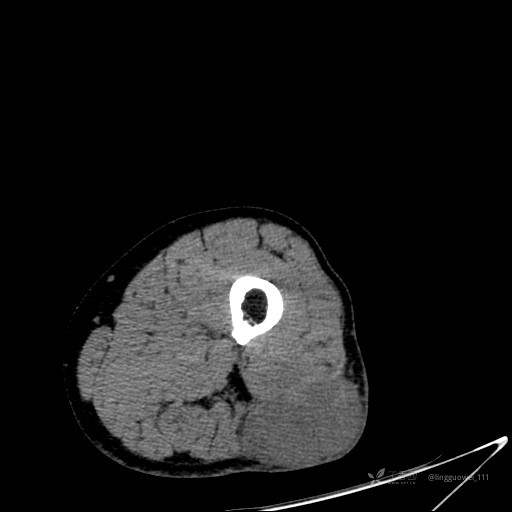

患者性别:男,85岁。发现大腿软组织肿块1年,增大3月,良性还是恶性?只有CT,能诊断正确吗?

增强动脉期